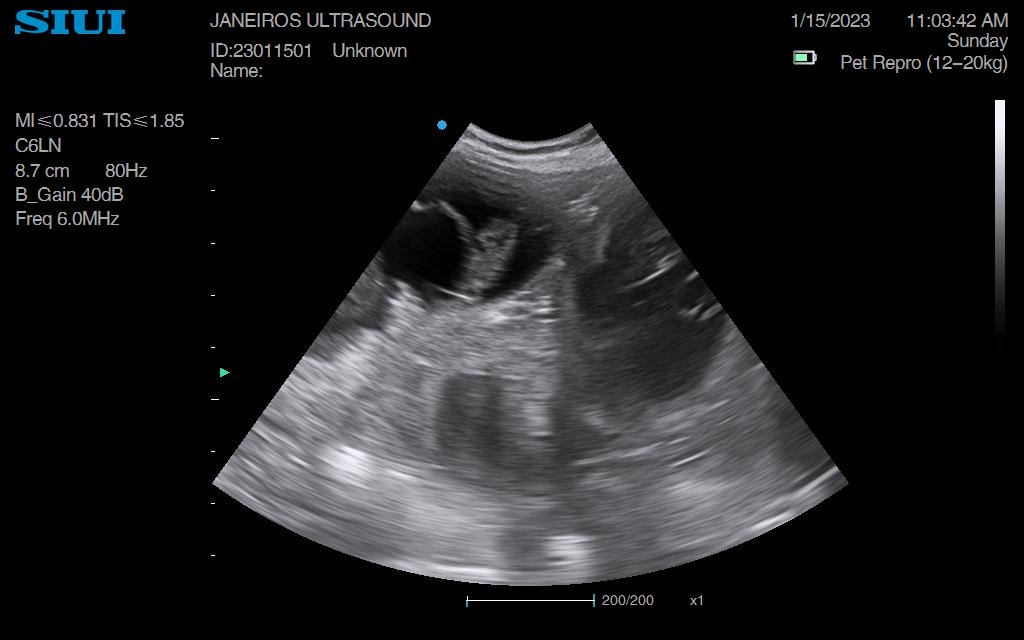

Spring forward to today. Measurements taken suggested 5wks and 1 day gestation and 6 sacs!!

Confirmed heartbeats on each puppy. All cooking away nicely.

The pictures and videos are so much clearer at this stage. Trust me.. don’t fib to you scanner regarding dates, it’s really not worth it! 😊